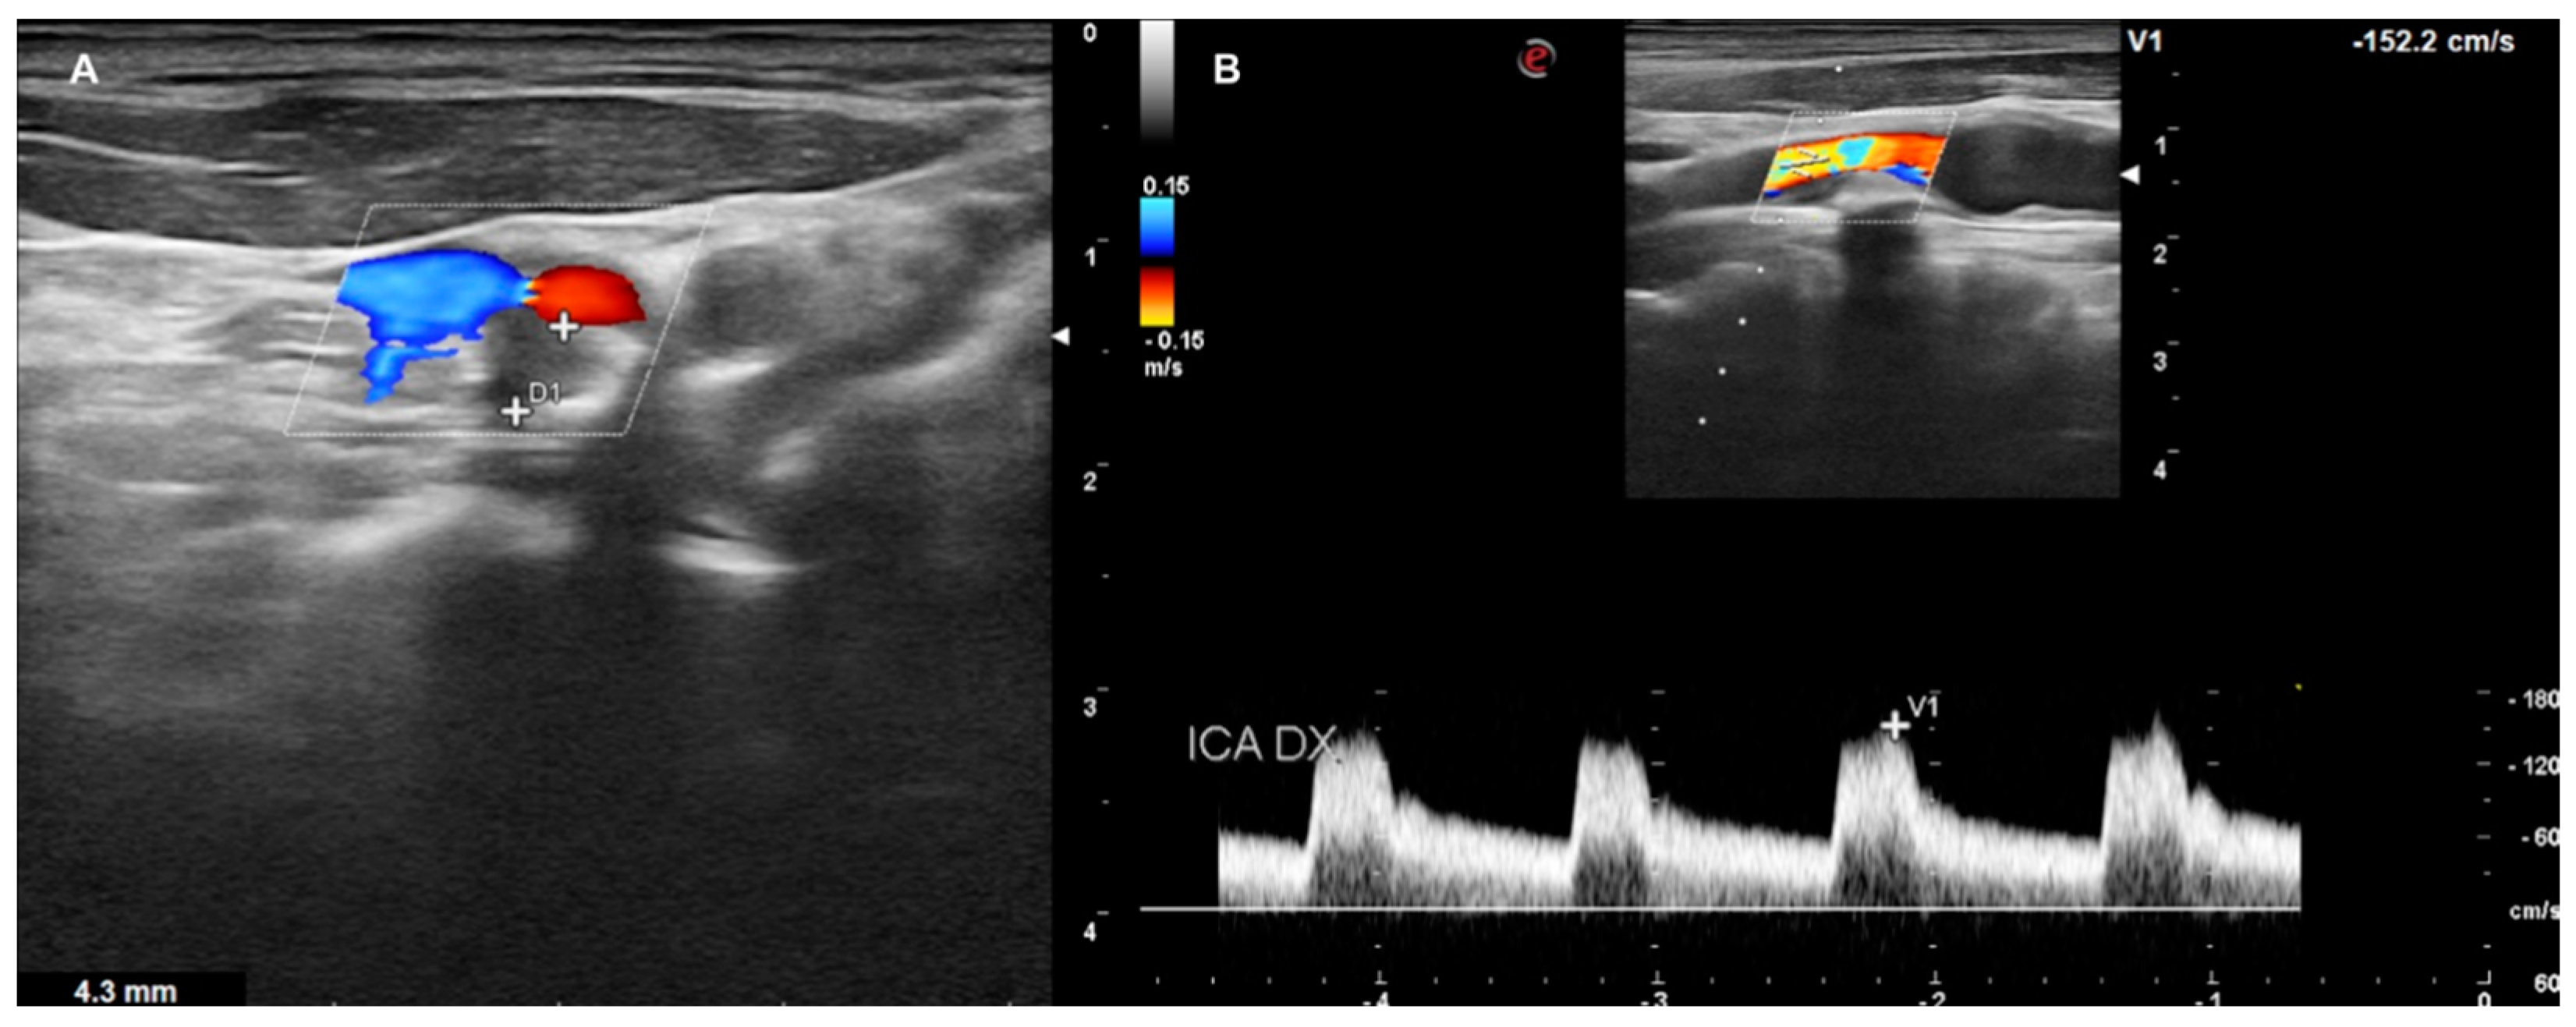

- LOW GRADE and MEDIUM GRADE: Patients presenting a carotid plaque under 30% of stenosis. In these cases, a cardiology evaluation was added, and a clinical path of the main arterial districts (aorta and peripheral arteries) was concluded by DUS (Figure 5 and Figure 6).

Figure 5. DUS images showing plaque in CCA—LOW GRADE (A), and its relative flow (B).

Figure 6. DUS images showing plaque in CCA—MEDIUM GRADE (A), and its relative flow (B).